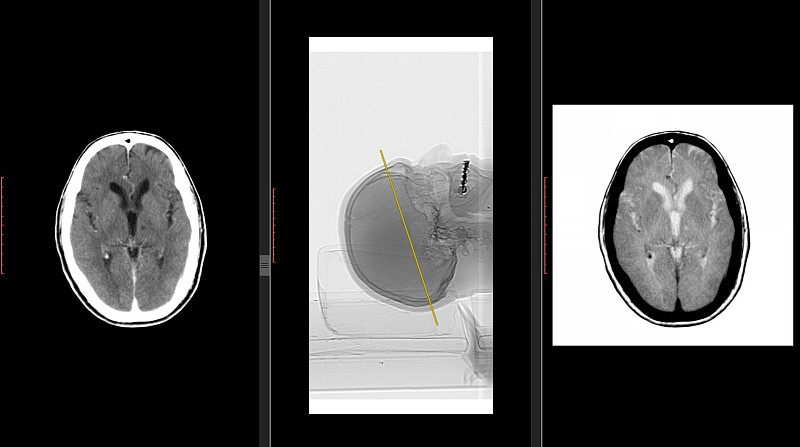

有X光扫描的手术室。详情

EPS